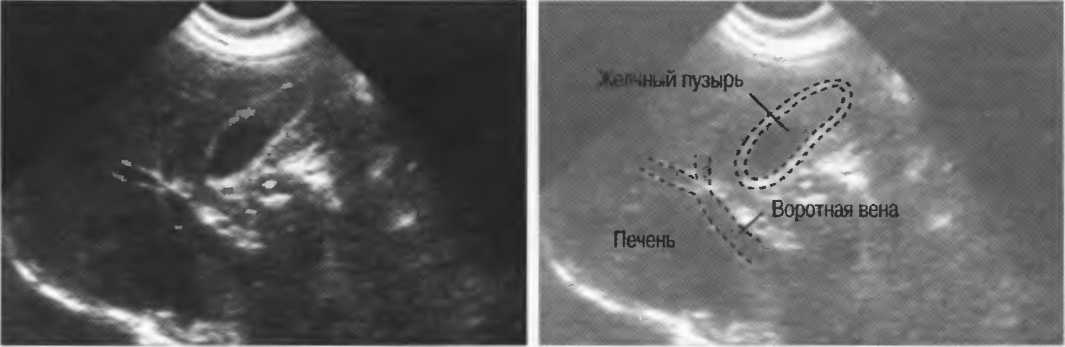

Рис. 10а. Жидкостьсодержащая структура — желчный пузырь, с задним усилением, имеющим место в результате низкого уровня затухания звукового сигнала в жидкости. Стенки желчного пузыря дают две боковые тени.